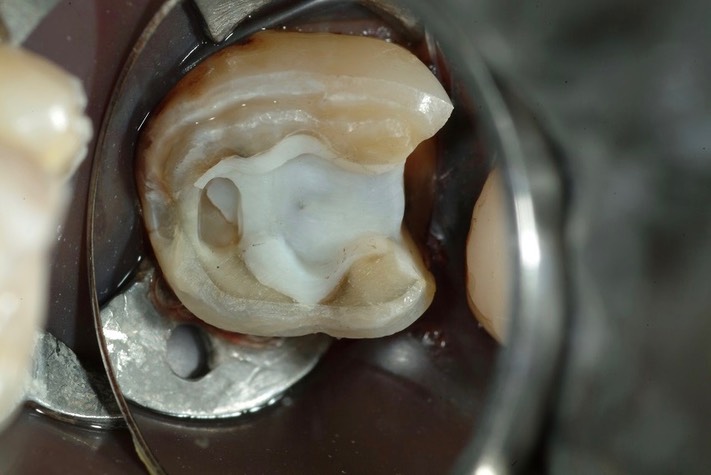

Larry Fujioka #31 prep